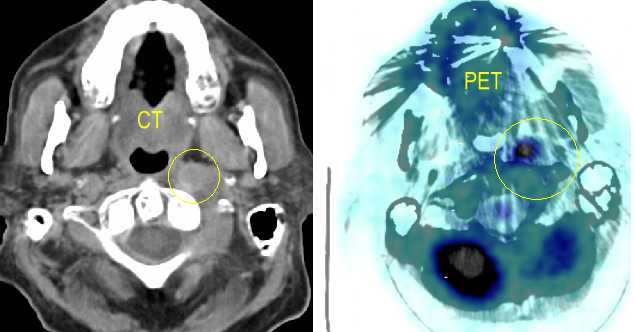

CT/PET relapse

Nasopharynx PET Scans, here , here , here, here, here, here